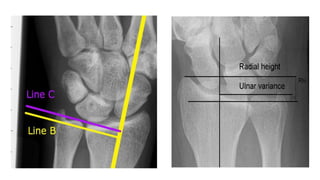

Radial Height & Inclination

Radial height is assessed on the PA view. It is a measurement between 2 parallel lines that are

perpendicular to the long axis of the radius. One line is drawn on the articular surface of the

radius, and the other is drawn at the tip of the radial styloid. The normal radial height is

9.9-17.3 mm.Measurements of less than 9 mm in adults suggest the presence of comminuted or

impacted fractures of the distal radius.

Radial inclination is measured on the PA view; this is a measurement of the radial angle. A line

is drawn along the articular surface of the radius perpendicular to the long axis of the radius,

and a tangent is drawn from the radial styloid. The normal angle is 15-25º.Abnormal

inclination of the distal radius may be a reflection of an impaction fracture of the distal radius

Ulnar variance (also known as Hulten variance) refers to the relative lengths of the distal articular

surfaces Ulnar variance may be:

● neutral (both the ulnar and radial articular surfaces at the same level)

● positive (ulna projects more distally)

● negative (ulna projects more proximally)

Normal ulnar variance is 9-12 mm & ulnar variance does not depend on the length of the ulnar